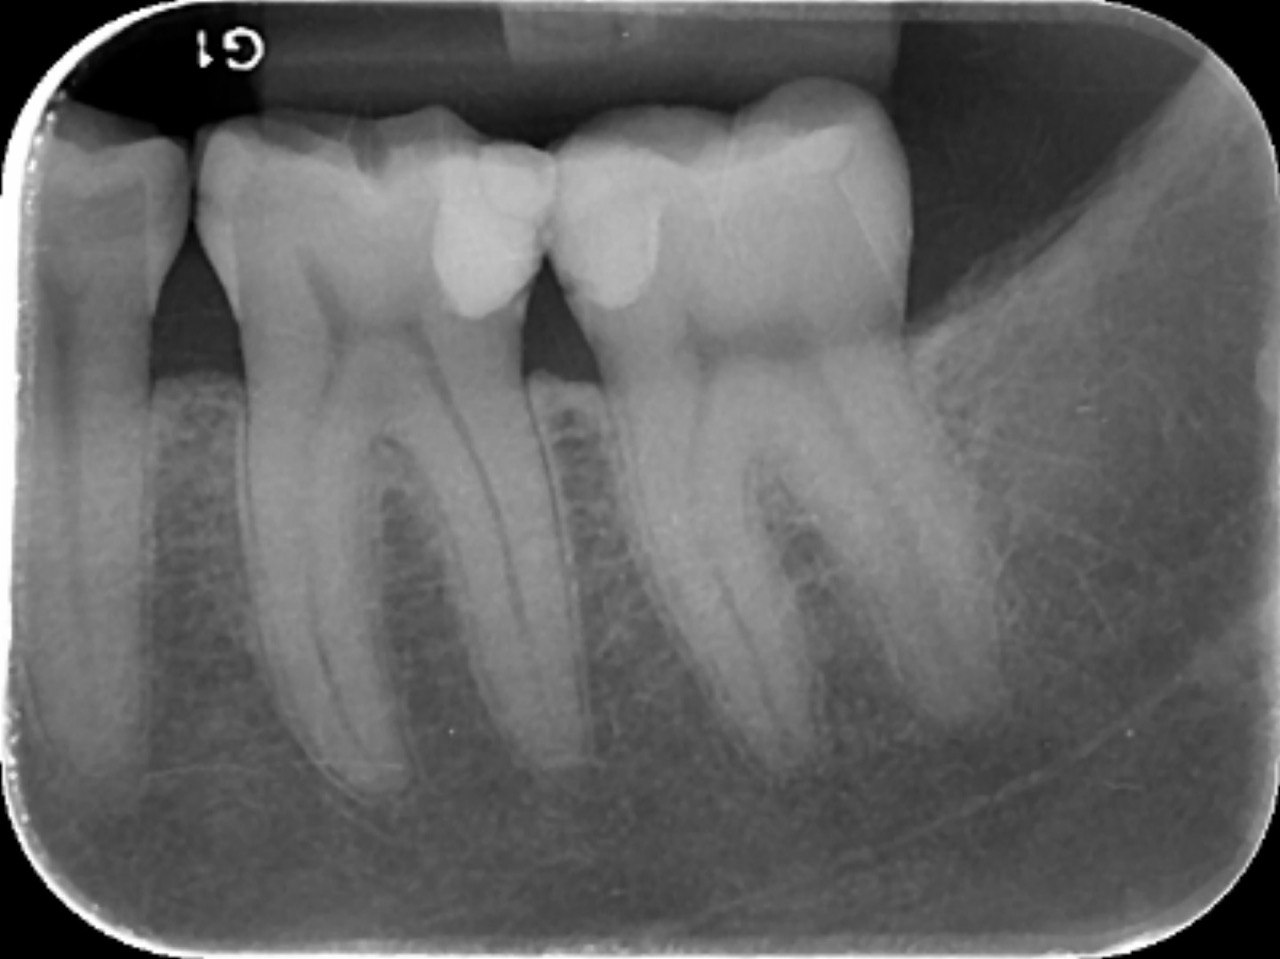

3. What is the caries level on the distal surface of the tooth # 3.6?

6: What is the caries level of mesial of the tooth # 3.6?

7: What is the caries level of Distal of the tooth # 3.6?

11. What is the caries level of the distal surface of the toot # 3.5?

16. What are the caries level in mesial and distal surfaces of the tooth # 4.6 respectively?

17. What is the Caries level on distal surface of the tooth # 3.5?

19. What are the caries level in mesial surface of tooth # 3.8 and distal surface of tooth # 3.7 respectively?

36. What is the caries level of the distal surface of the tooth # 3.4 and mesial surface of the tooth # 3.5 respectively?

37. What is the caries level of distal of the tooth # 3.6?

39. What are the caries level in distal surface of the tooth # 3.4 and mesial surface of the tooth # 3.5?